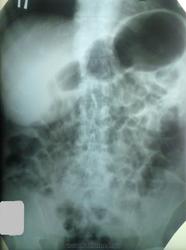

Вот обзорная и обзорная при ирригоскопии с прошлого раза.

Вот начало сегодняшнего исследования...через 20 минут и через 1 час

Снимки через 2 часа 30 минут и 4 часа 30 минут